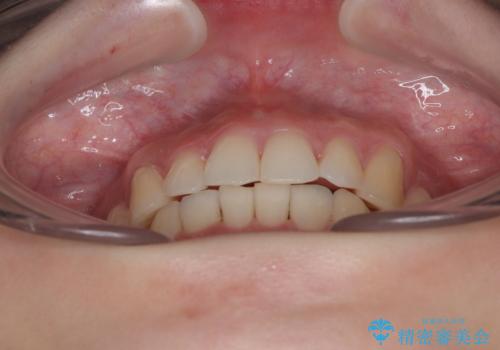

- 前歯のデコボコを気にして来院された患者様です。

全体的にデコボコが多く、特に下の前歯は隠れてしまうほどの状態でした。

左右ともに奥歯の咬み合わせが理想的な位置にあったこともあり、患者様のご希望通り、インビザラインにて矯正治療を行うこととしました。

マウスピース矯正特有の、奥歯が噛みにくくなるという現象の解消に少し期間をいただきましたが、日々の装着時間を遵守していただき、綺麗な歯列に整えることができました。